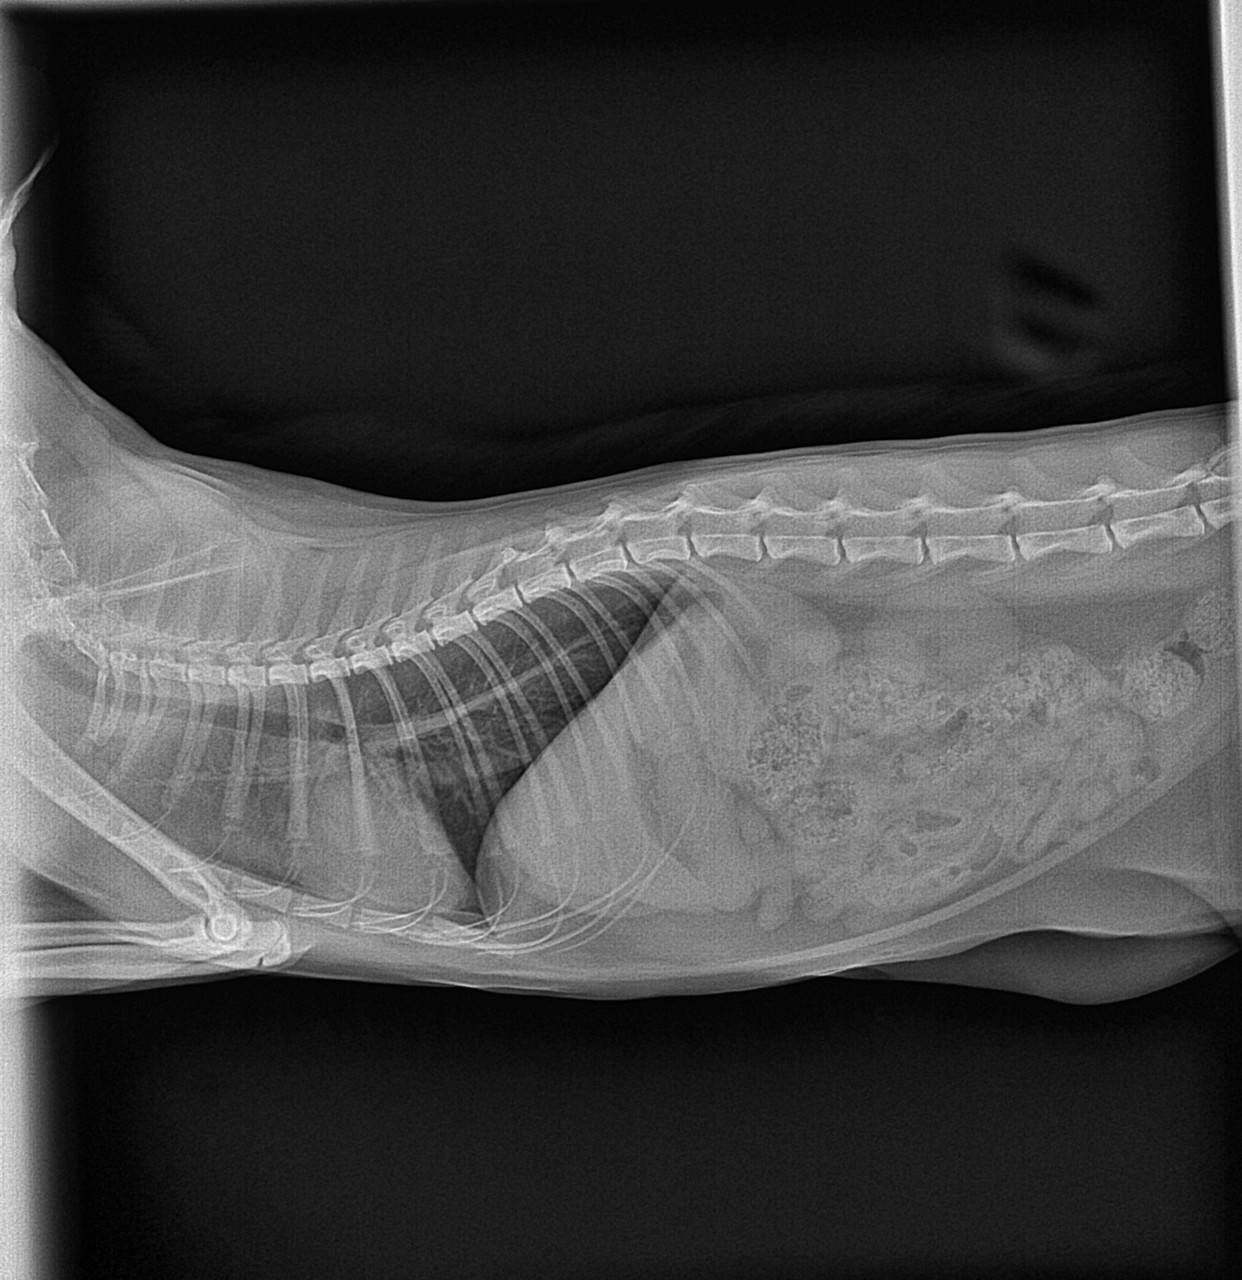

Сделали рентген и узи сердца, ничего не выявили, прикладываю фото рентгена можете пожалуйста проверить

Здравствуйте. По снимку сердце и лёгкие выглядят без выраженных патологий, отёка или плеврита не видно. Однако, если у кота сохраняются хрипы при дыхании, несмотря на нормальные рентген и УЗИ, стоит исключить ларингоспазм, хронический ринит, аллергические реакции или новообразования в носоглотке  рекомендуется эндоскопия дыхательных путей или консультация ЛОР-ветврача.

Здравствуйте. На снимке всё хорошо, значит хрипы скорее всего из-за бронхита или астмы  рекомендую пробный курс ингаляционных кортикостероидов (будесонид) и бронходилататоров, а при сохранении симптомов  трахеальная промывка и флюорографию.